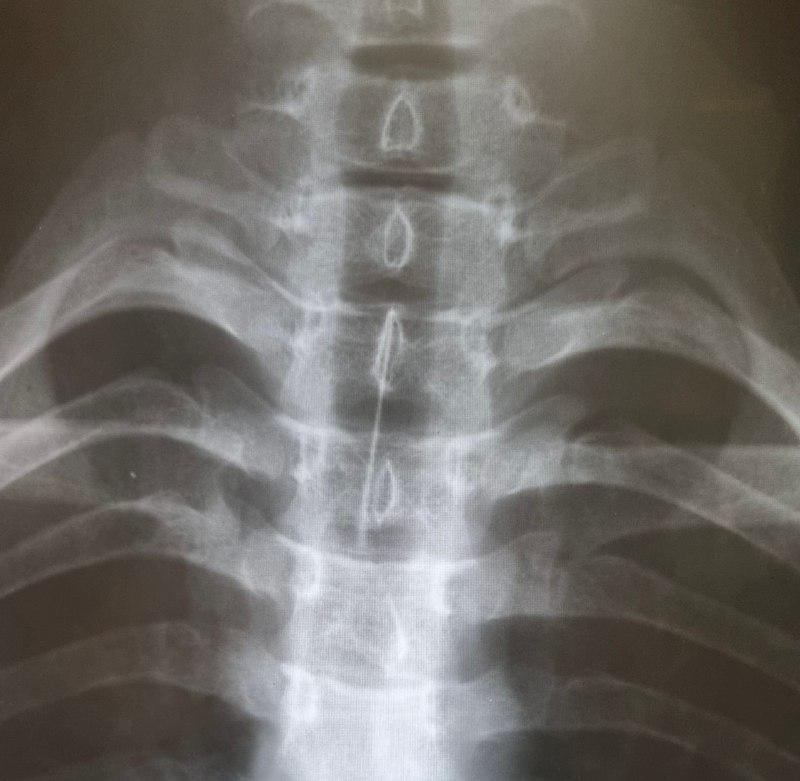

Подростка срочно повезли на рентген-исследование в больницу Ангарска, определили местонахождение опасного предмета – игла застряла в главном бронхе. Для ее извлечения мальчика экстренно привезли в Иркутск.